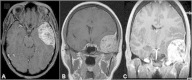

Background Aneurysmal bone cysts (ABCs) are benign bony lesions that rarely affect the skull base. Very few cases of temporal bone ABCs have been reported. We describe the first case of a temporal bone ABC that was thought to be consistent with a meningioma based on preoperative magnetic resonance imaging (MRI) findings. Clinical Presentation An otherwise healthy 23-year-old woman presented with a pulsatile noise in her left ear and a 4-week history of throbbing headache with nausea. There was no associated emesis, visual or auditory changes, or other neurologic features. Neurologic examination revealed a left lower motor neuron facial paresis. Computed tomography and MRI studies demonstrated a large lesion in the left middle cranial fossa skull base with erosion of the petrous temporal bone. Based on the presence of a "dural tail" on preoperative contrast-enhanced T1-weighted imaging, the lesion was interpreted to likely be consistent with a meningioma. An orbitozygomatic approach was utilized for surgical excision. Histopathologic evaluation was consistent with an ABC. Conclusion Postoperatively the patient had improvement in the lower motor neuron facial paresis. It is important to consider ABC in the differential diagnosis of intracranial lesions accompanied by the dural tail sign on MRI.